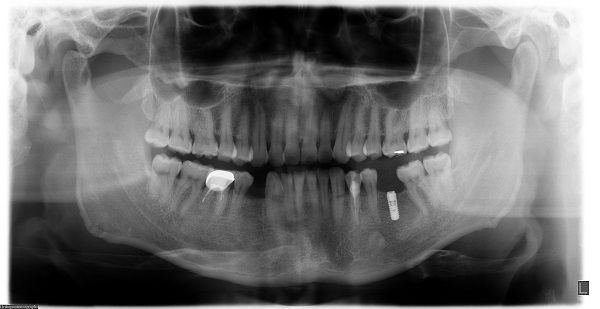

种植牙是将纯钛金属制成的人工牙根(种植体)一端通过微创外科手术植入缺牙部位的牙槽骨内,经过一段愈合期后,人工牙根和颌骨结合,再在人工牙根上镶装义齿。成功的种植牙不仅具有形态逼真、美观、舒适、咀嚼功能好、损伤邻牙等优势,还是目前理想的修复治疗方式,被誉为继乳牙、恒牙后“人类的第三副牙齿”。